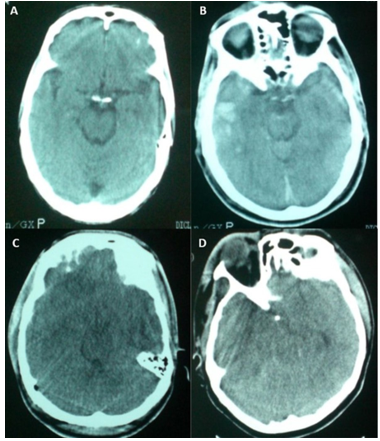

Cranial CT imaging was performed using a Toshiba Xvision/GX scanner. All scans were obtained without contrast enhancement. Slice thickness was set at 5 mm for the posterior fossa and 10 mm for the supratentorial region, parallel to the orbitomeatal line. Evaluation of basal cisterns was performed according to the classification system originally proposed by Toutant et al. [19], which categorizes cisternal appearance as compressed, obliterated, or absent (Figure 1).

Figure 1

Figure 1. Representative cranial CT images demonstrating the status of the mesencephalic cisterns. A: Normal basal cisterns with preserved anatomical contours. B: Compressed cisterns, indicating increased intracranial pressure. C: Obliterated cisterns, reflecting severe cisternal narrowing. D: Non-visualized cisterns, consistent with complete effacement due to critical intracranial hypertension